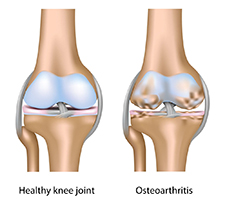

Chondroitin Sulfate

is a glycosaminoglycan (GAG), a class of molecules very important in joint health. Current research indicates that chondroitin sulfate may improve joint function and is especially effective for pain reduction in osteoarthritis patients. There is also evidence that chondroitin sulfate inhibits the enzymes that are known to degrade cartilage and helps support the synthesis of new cartilage for repair.

Chondroitin Sulfate

is a glycosaminoglycan (GAG), a class of molecules very important in joint health. Current research indicates that chondroitin sulfate may improve joint function and is especially effective for pain reduction in osteoarthritis patients. There is also evidence that chondroitin sulfate inhibits the enzymes that are known to degrade cartilage and helps support the synthesis of new cartilage for repair.

It is estimated that one in three US adults, or 69.9 million people, suffer from some kind of chronic joint problem. Every adult, as well as many adolescents, have experienced some type of joint pain. Whether it was a sore knee or elbow, joint pain is very uncomfortable. Some joint pain is temporary and can be relieved with little treatment, but for those suffering from chronic joint pain, finding ways to ease it can be very challenging.

Causes and Symptoms Associated With Joints

Inflammation is the swelling of the joint and the surrounding area. This may occur from excessive use of the joint. Both stress and inflammation can cause pain in the joint.